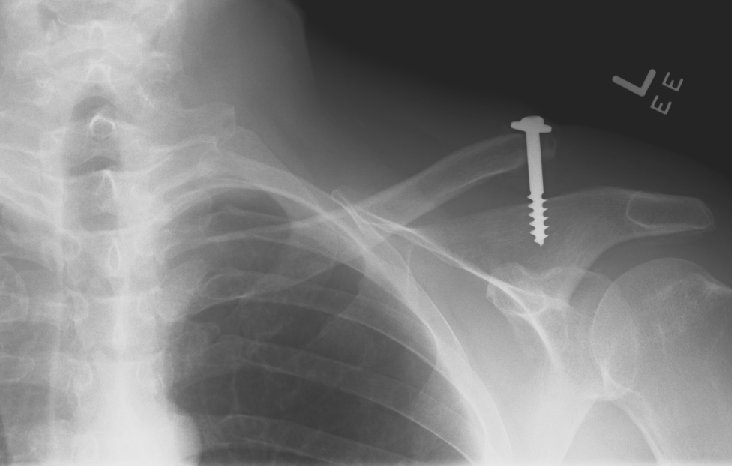

Return to Acromioclavicular Joint Separation